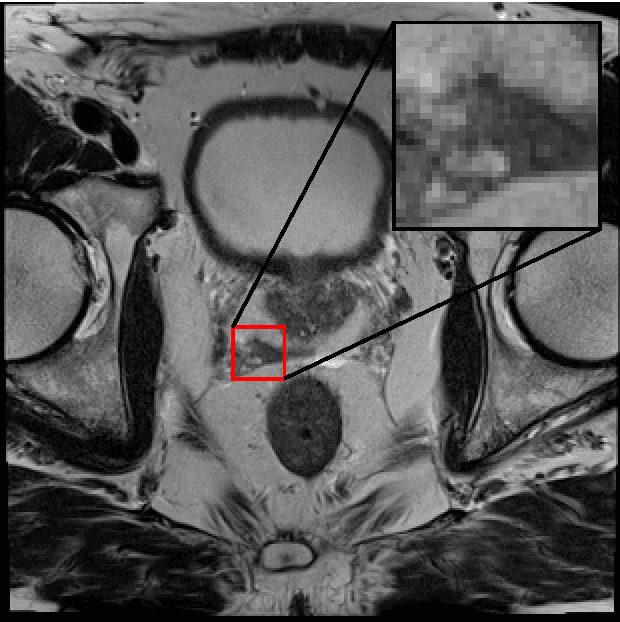

Abstract:Generative Adversarial Neural Networks (GANs) are applied to the synthetic generation of prostate lesion MRI images. GANs have been applied to a variety of natural images, is shown show that the same techniques can be used in the medical domain to create realistic looking synthetic lesion images. 16mm x 16mm patches are extracted from 330 MRI scans from the SPIE ProstateX Challenge 2016 and used to train a Deep Convolutional Generative Adversarial Neural Network (DCGAN) utilizing cutting edge techniques. Synthetic outputs are compared to real images and the implicit latent representations induced by the GAN are explored. Training techniques and successful neural network architectures are explained in detail.